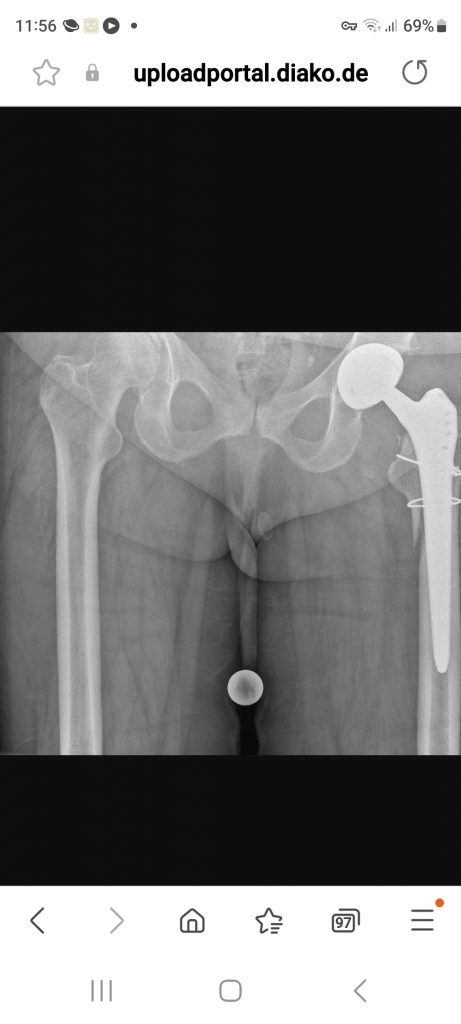

Dort musste Johanne noch 5 Tage warten, bis der Chefarzt der Orthopädie aus dem Urlaub zurück war; die Chirurgen haben sich nicht an ihre Fraktur getraut! Aber endlich hat er sie dann erfolgreich operiert:

Johanne brauchte 10 Tage, um sich von dieser schweren OP zu erholen, bis sie in die BG-REHA-Klinik nach SANKT PETER-ORDING verlegt werden konnte. Die REHA dauerte nicht die üblichen 3 Wochen, sondern fünf, bis sie nach über 10 Wochen wieder nach Hause kam: